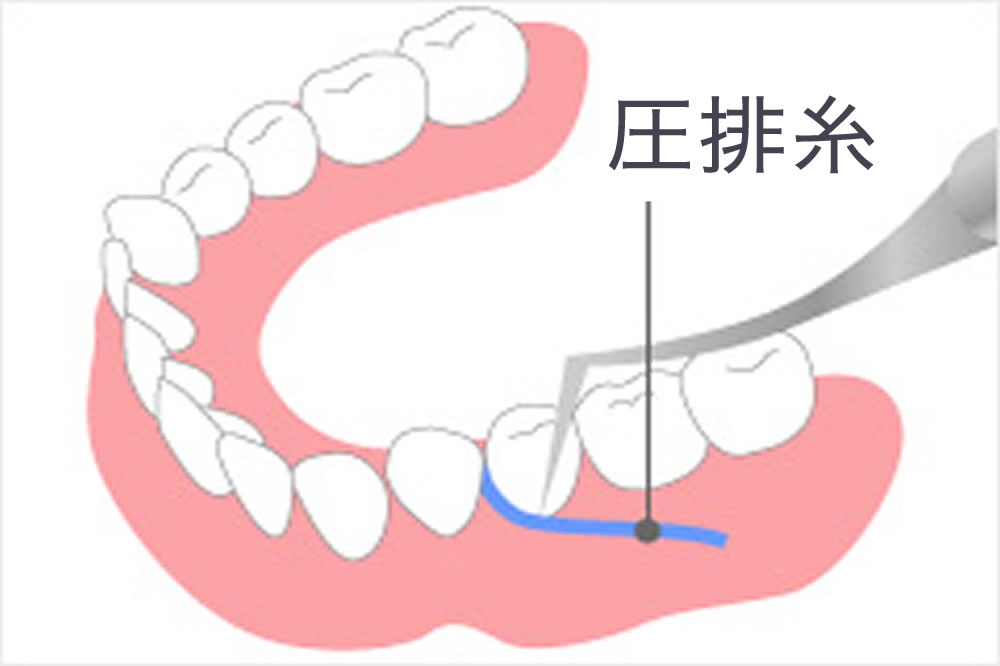

歯肉圧排(しにくあっぱい)

歯肉を押し下げながら補綴物を装着し、高い適合性を目指します。

歯肉を押し下げながら補綴物を装着し、高い適合性を目指します。